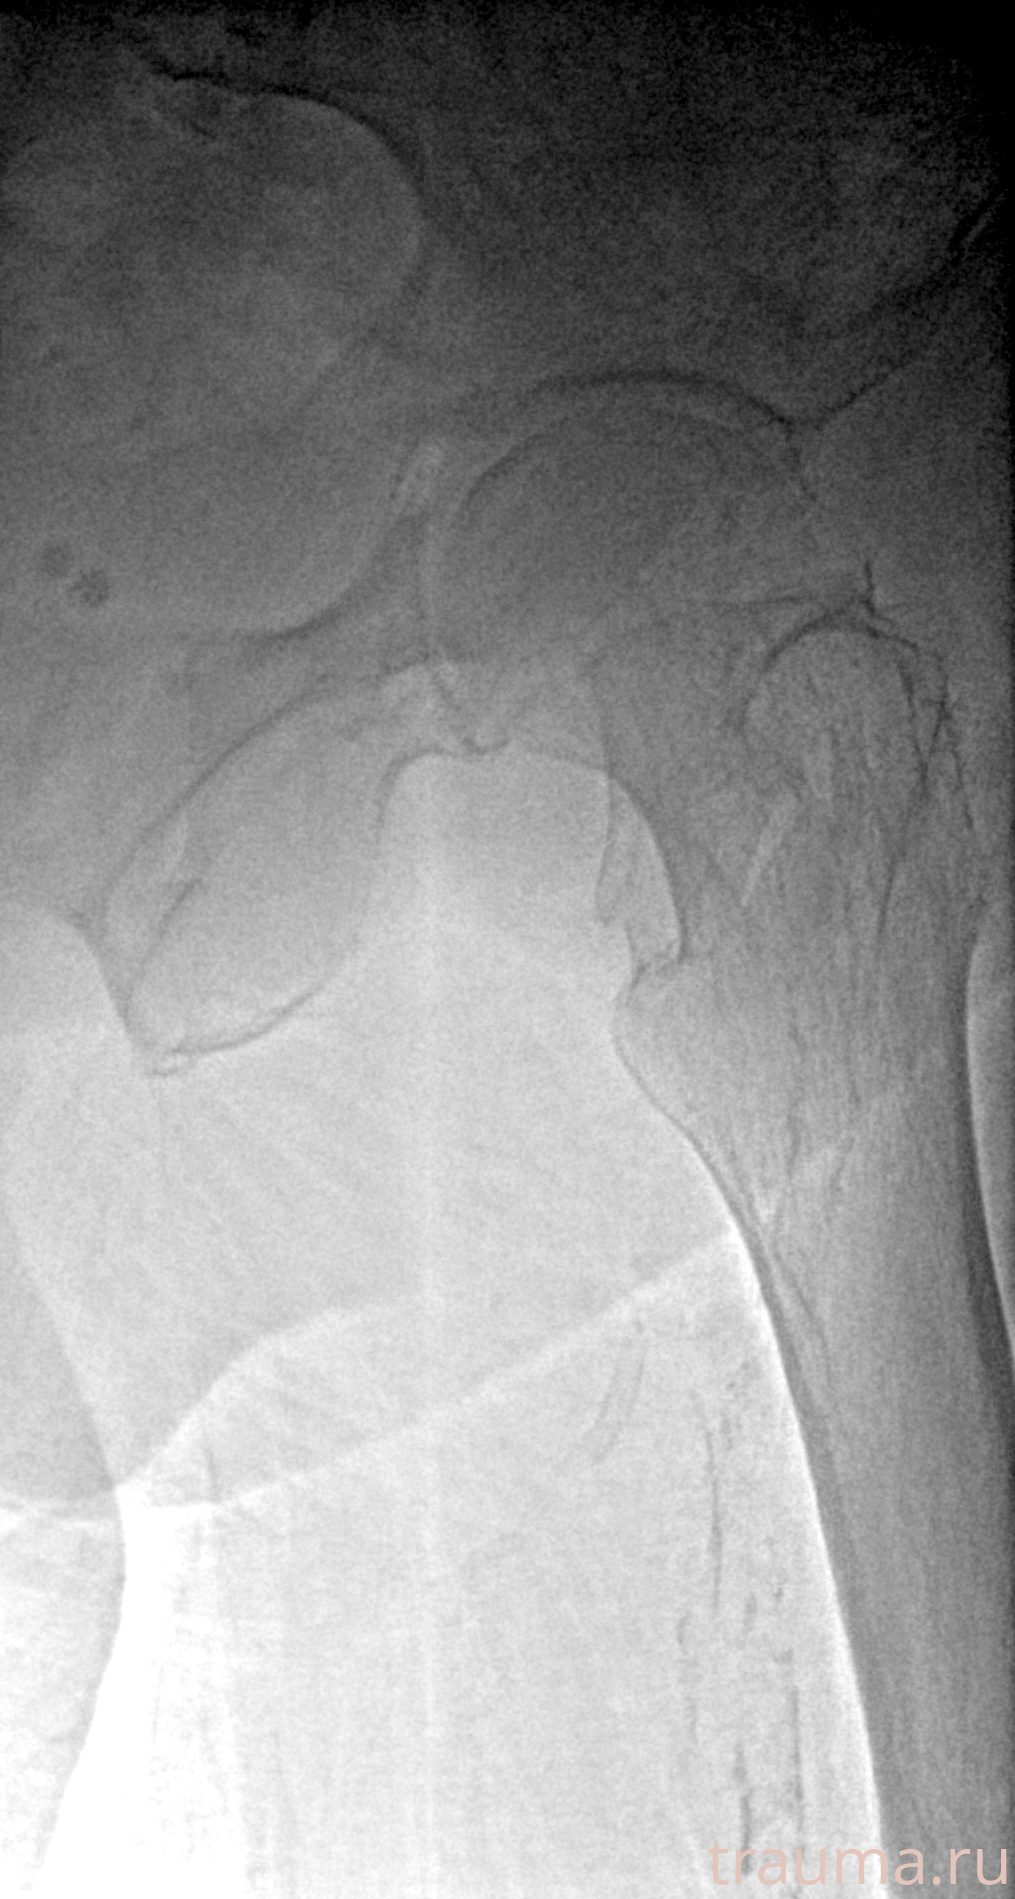

Рентген на дому: по вашему адресу приезжает врач-рентгенолог, травматолог-ортопед с мобильным рентгеновским аппаратом, проводит диагностику травмы или заболевания, делает необходимые рентгенограммы, дает рекомендации по дальнейшему лечению. Получить качественные снимки в домашних условиях возможно благодаря уникальной методике, разработанной МосРентген Центром для института  Склифосовского